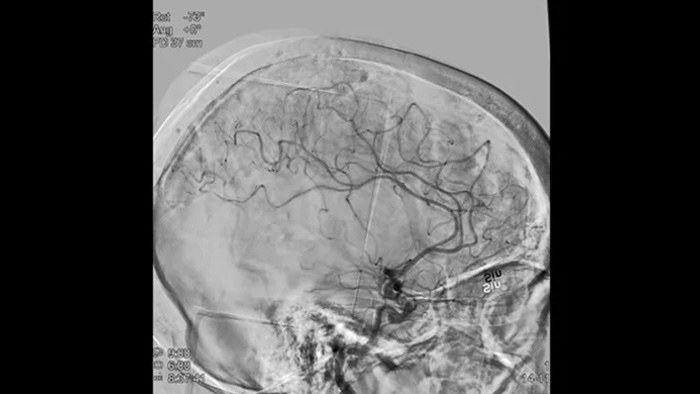

SmartCT Vaso позволяет проводить визуализацию за пределами тромба с помощью перипроцедурного создания изображений дистальных сосудов при ишемическом инсульте. SmartCT Vaso — это метод сбора данных, основанный на получении КТ-изображений с помощью конического пучка и внутриартериальной инъекции контраста. Технология позволяет проводить визуализацию за пределами тромба с помощью перипроцедурного создания изображений дистальных сосудов при ишемическом инсульте. При ретроградном наполнении становится видна структура сосудов до и после тромба. 3D-схема сосудов SmartCT Vaso может использоваться при визуализации устройств для извлечения тромба.

Технология SmartCT Roadmap предоставляет данные изображений анатомических структур, обеспечивая точность навигации при проведении к тромбу проводника, катетера и специального устройства.